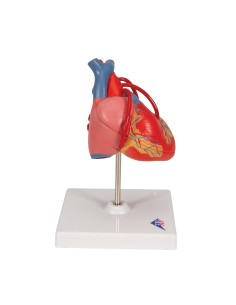

Dal cranio in 22 parti con incastri magnetici ai modelli di colonna vertebrale, da quelli di articolazioni a quelli di cuore, ogni pezzo della nostra collezione è progettato per un’immersione totale nello studio dell’anatomia umana. I nostri modelli, realizzati tramite scansioni di ossa vere, garantiscono un’esperienza tattile autentica e una fedeltà di peso quasi identica agli originali.